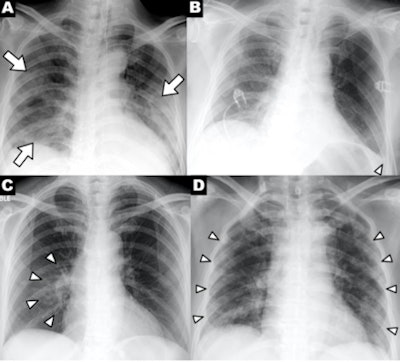

A series of chest x-ray findings of a patient with COVID-19 demonstrating clinical characteristics of disease: (A) patchy consolidations, (B) pleural effusion, (C) perihilar distribution, and (D) peripheral distribution. Images courtesy of RSNA.The researchers said that clinicians should keep the study's findings in mind when interpreting chest x-rays of suspected COVID-19 patients, or when deciding which imaging modality to use.

The researchers analyzed images from 64 patients who were seen at four Hong Kong hospitals from January-March 2020. They found that signs of COVID-19 on chest radiography were similar to those of CT: bilateral, peripheral consolidation and/or ground-glass opacities. Consolidation was the most common finding on x-ray in 47% of patients, while ground-glass opacities were found in 33%.

Clinical features on radiography. What features on x-ray are indicative of COVID-19? Chest radiography can show patchy or diffuse asymmetric airspace opacities that are similar to pneumonia caused by other coronaviruses, according to a March 23 article by Dr. Jonathan Rodrigues, PhD, and colleagues in Clinical Radiology.

Meanwhile, researchers from the University of Washington in Seattle have provided a list of the top five findings on chest x-ray of COVID-19. The most common finding was bilateral reticular nodular opacities, found in 52% of cases, followed by ground-glass opacities in 48%. Some 72 hours after admission, these findings rose to 86% for reticular nodular opacities and 67% for ground-glass opacities, they wrote in a study published March 19 in JAMA.